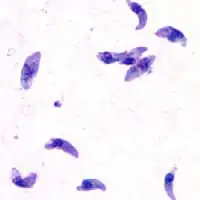

| T. gondii tachyzoites | |

Acute toxoplasmosis is often asymptomatic in healthy adults.[13][14] However, symptoms may manifest and are often influenza-like: swollen lymph nodes, headaches, fever, and fatigue,[15] or muscle aches and pains that last for a month or more. It is rare for a human with a fully functioning immune system to develop severe symptoms following infection. People with weakened immune systems are likely to experience headache, confusion, poor coordination, seizures, lung problems that may resemble tuberculosis or Pneumocystis jiroveci pneumonia (a common opportunistic infection that occurs in people with AIDS), or chorioretinitis caused by severe inflammation of the retina (ocular toxoplasmosis).[15] Young children and immunocompromised people, such as those with HIV/AIDS, those taking certain types of chemotherapy, or those who have recently received an organ transplant, may develop severe toxoplasmosis. This can cause damage to the brain (encephalitis) or the eyes (necrotizing retinochoroiditis).[16] Infants infected via placental transmission may be born with either of these problems, or with nasal malformations, although these complications are rare in newborns. The toxoplasmic trophozoites causing acute toxoplasmosis are referred to as tachyzoites, and are typically found in various tissues and body fluids, but rarely in blood or cerebrospinal fluid.[17]

While rare, skin lesions may occur in the acquired form of the disease, including roseola and erythema multiforme-like eruptions, prurigo-like nodules, urticaria, and maculopapular lesions. Newborns may have punctate macules, ecchymoses, or "blueberry muffin" lesions. Diagnosis of cutaneous toxoplasmosis is based on the tachyzoite form of T. gondii being found in the epidermis.[30] It is found in all levels of the epidermis, is about 6 by 2 μm and bow-shaped, with the nucleus being one-third of its size. It can be identified by electron microscopy or by Giemsa staining tissue where the cytoplasm shows blue, the nucleus red.[31]

In its lifecycle, T. gondii adopts several forms.[32] Tachyzoites are responsible for acute infection; they divide rapidly and spread through the tissues of the body. Tachyzoites are also known as "tachyzoic merozoites", a descriptive term that conveys more precisely the parasitological nature of this stage.[33] After proliferating, tachyzoites convert into bradyzoites, which are inside latent intracellular tissue cysts that form mainly in the muscles and brain. The formation of cysts is in part triggered by the pressure of the host immune system.[34] The bradyzoites (also called "bradyzoic merozoites") are not responsive to antibiotics. Bradyzoites, once formed, can remain in the tissues for the lifespan of the host. In a healthy host, if some bradyzoites convert back into active tachyzoites, the immune system will quickly destroy them. However, in immunocompromised individuals, or in fetuses, which lack a developed immune system, the tachyzoites can run rampant and cause significant neurological damage.[32]